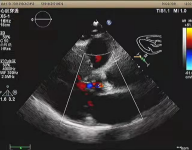

心脏彩超

峰值流速度:415 cm/s;

最高跨瓣压差:69 mmHg;

平均跨瓣压差:42 mmHg;

左室射血分数EF值:55%;

左室舒张末期内径(LVD):56 mm;

主动脉瓣评估:主动脉瓣严重钙化,主动脉瓣二叶瓣畸形,主动脉重度狭窄伴关闭不全。

瓣膜完全释放,无瓣周漏